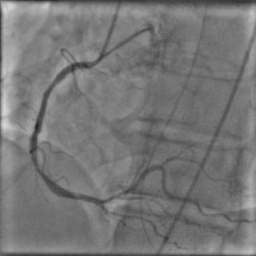

X-ray angiography is the most used imaging modality to visualise blood vessels for interventional purposes such as stenting of stenosed vessels or for diagnostic purposes such as assessment of myocardial perfusion or stenosis grading. To minimise ionising radiation exposure of the patient and medical personnel during image acquisition, low power X-Rays are used resulting in noisy and low contrast images. In the context of diagnosis, the main object of interest is the vascular tree, its branchings and variations in thickness. It is therefore necessary to accurately highlight the vessels in consecutive frames to reduce the noise and improve contrast. In addition, in interventional procedures, identifying interventional instruments (catheter, wires) is also needed in order to better plan and control their positioning. Efficiently discriminating between instruments and vessels as well as other anatomical structures that may have similar appearance is crucial during the interventions. Figure 1(a-c) shows an example of an angiogram sequence. Note large non-rigid motion between frames as well as the ambiguity between vessels and the catheter. Figure 1(e) shows a frame from a different sequence of the same patient but taken at different scan and angle and (f) shows a different patient. There is a significant difference in vessel as well as catheter locations in all three sequences, which we consider as independent examples. Figure 1(d) shows the ground truth segmentation of the first frame.

The dataset consists of anonymised fluoroscopy X-Rays of 26 different patients. The images were acquired during stent placement using a General Electric Innova 2000 system and stored according to standard medical protocol in DICOM format. In total the dataset includes 36000 frames corresponding to 365 distinct video sequences with an average of 98 frames each. Different sequences of the same patient were taken at different angles and stages of the procedure therefore they differ significantly as shown in Figure 1(c)(e)(f). Each frame is rescaled from to due to memory constraints.